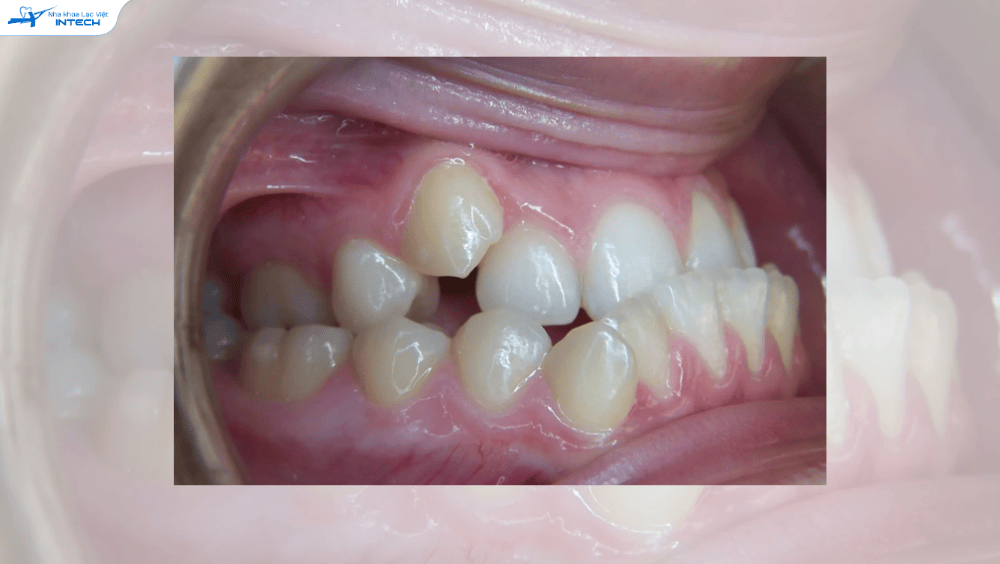

2. Khớp cắn ngược

Hay còn gọi là móm, là khi răng hàm dưới ở phía ngoài so với răng hàm trên. Nâng khớp cắn giúp loại bỏ sự cản trở giữa hai hàm, tạo điều kiện thuận lợi cho răng hàm trên di chuyển ra ngoài và răng hàm dưới di chuyển vào trong, đưa khớp cắn về vị trí đúng.

70% khách hàng Khách hàng bị khớp cắn sâu "nắt buộc" phải nâng khớp